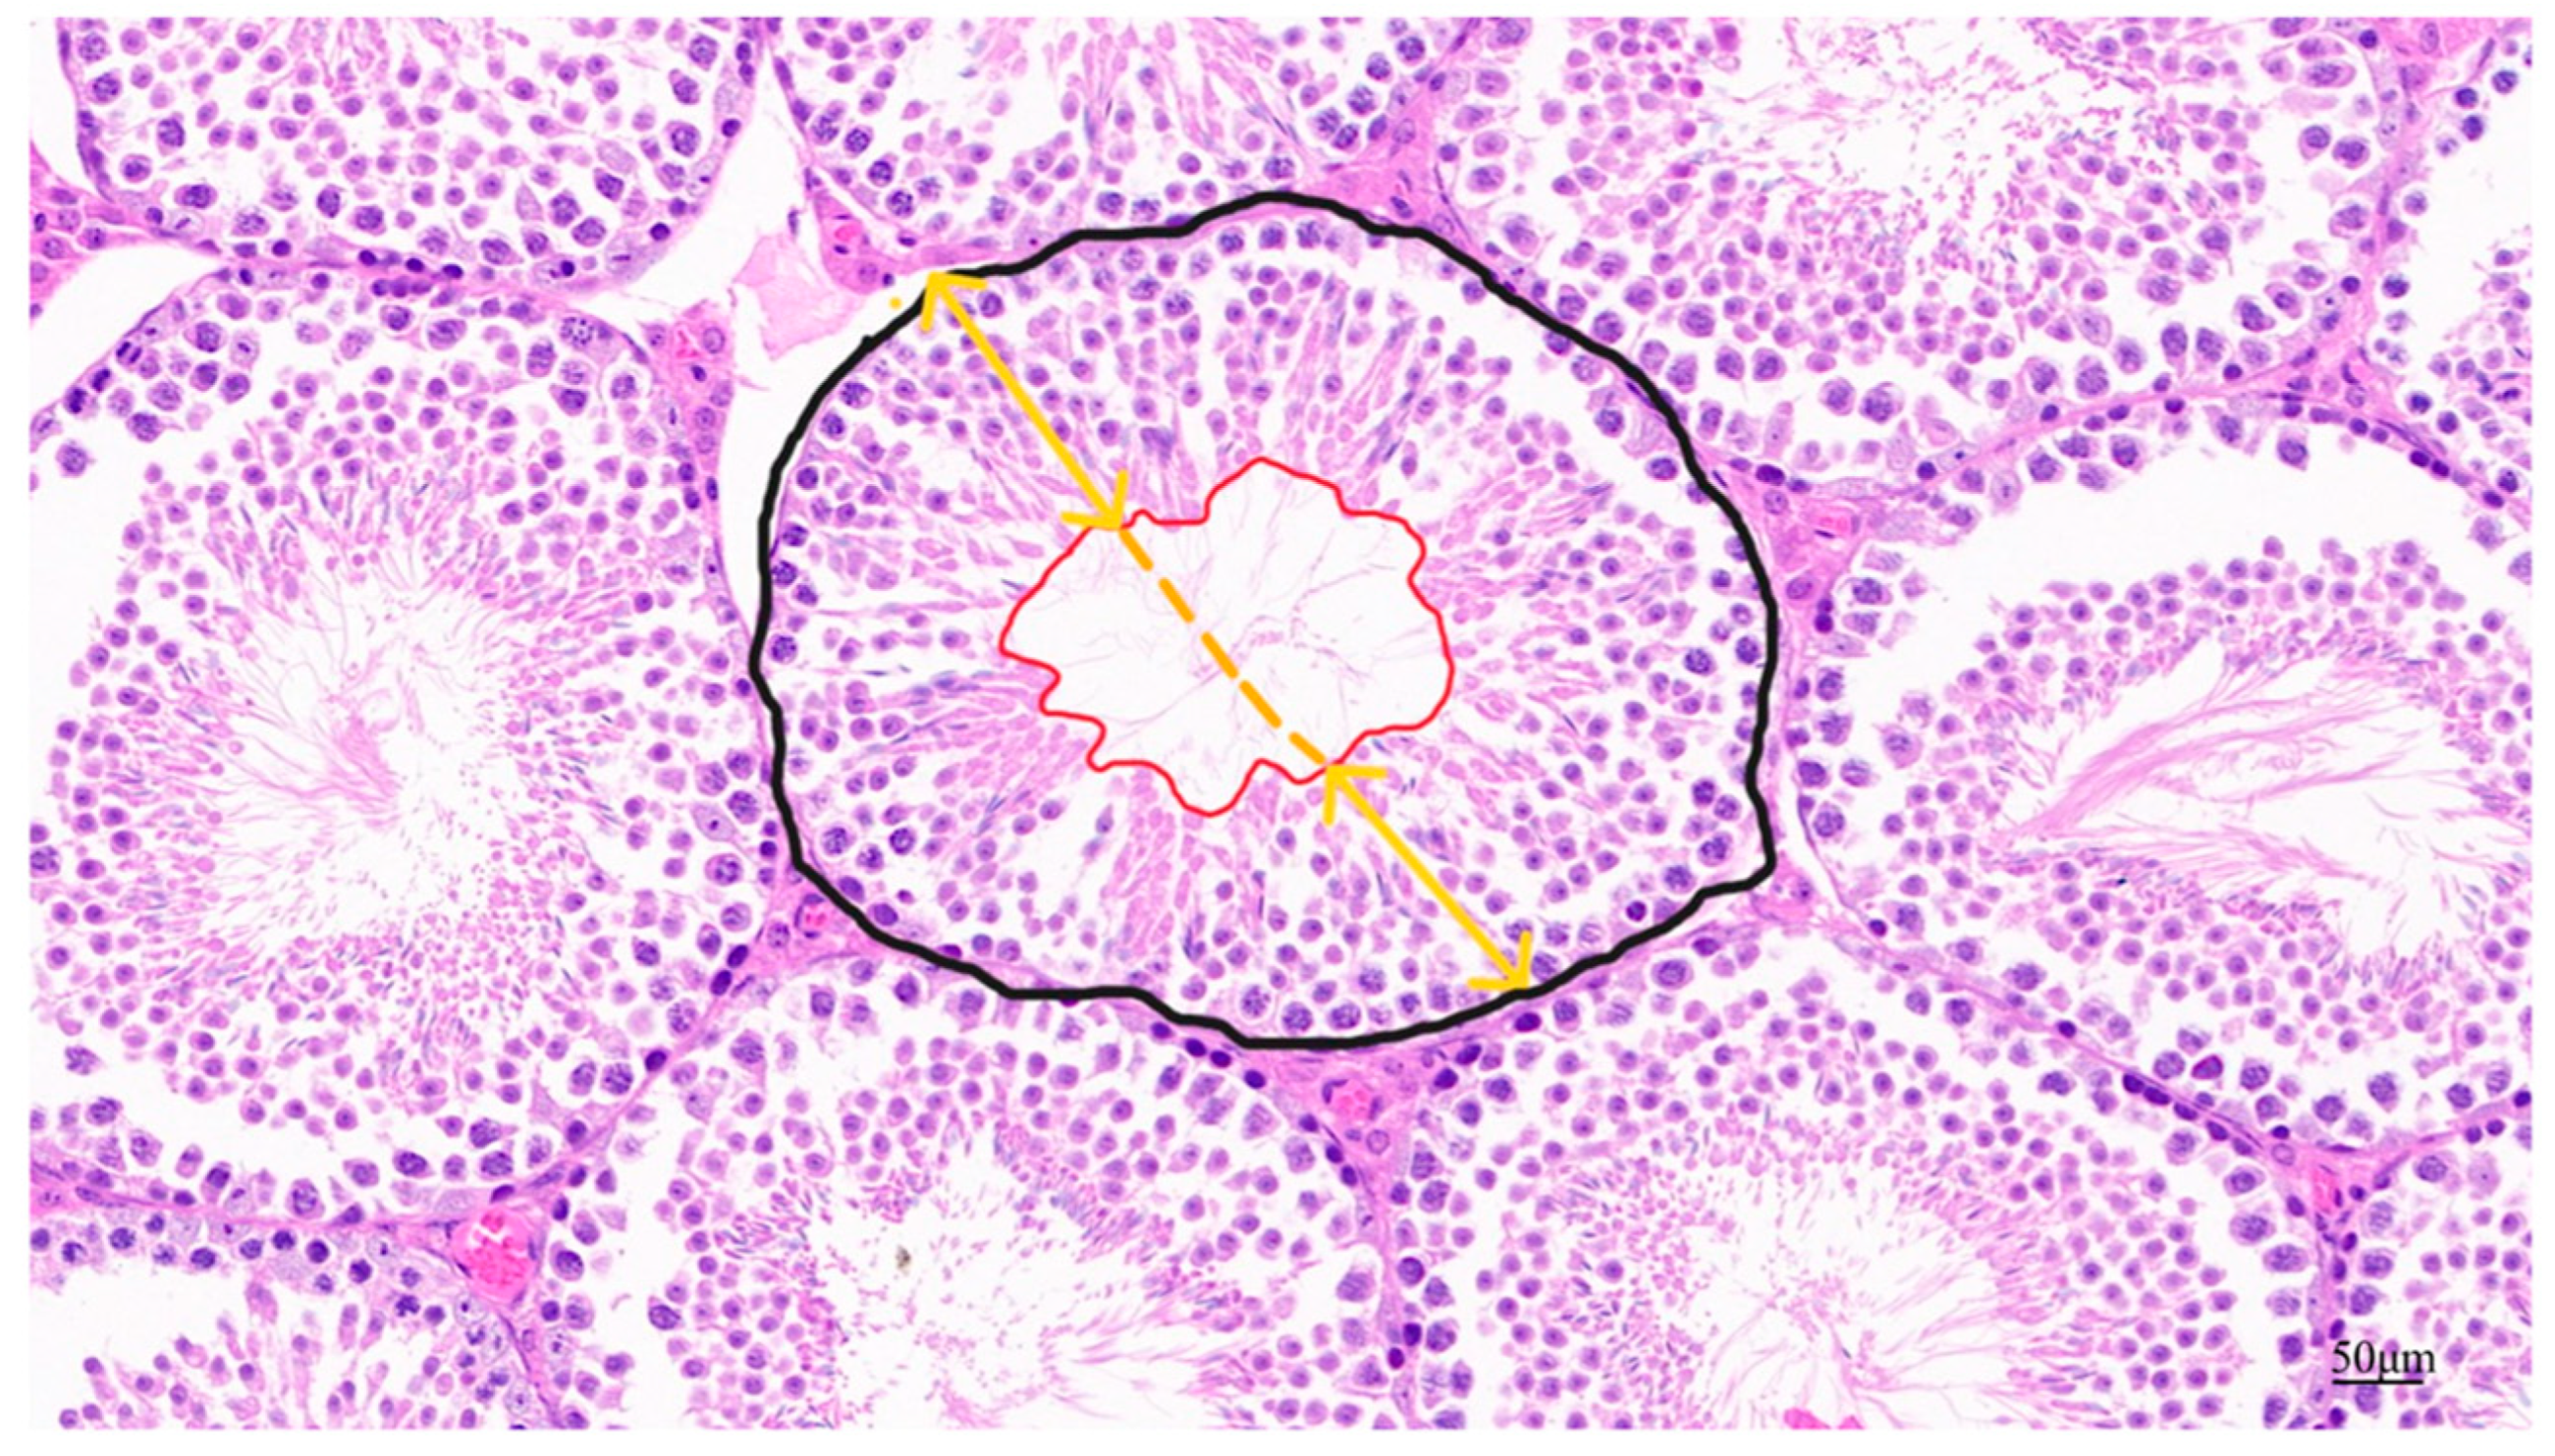

Fixed testicular tissue slides were stained with hematoxylin and eosin and photographed under light microscopy. Testicular tissue lumen area, seminiferous tubular area, epithelial height, and diameter were assessed. The black line area shown in Figure 2 indicates the cross-sectional area of the spermatogenic tubules and the red line area is the lumen area. The yellow line represents the vertical diameter of the varicocele, and the average length of the solid portion of the line represents the height of the varicocele epithelium [24]. Apoptosis in testicular paraffin sections was identified using a TUNEL staining kit (Servicebio, Wuhan, China) according to the instructions and the sections were analyzed using confocal fluorescence microscopy.

Figure 2.

Schematic diagram of parameters for quantitative assessment of testicular tissue in male mice.